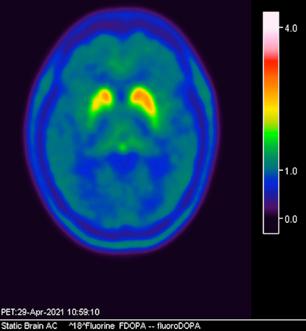

Femenino de 65 años, antecedente de hipertensión arterial de 20 años de evolución en control. Sin antecedentes familiares relevantes de enfermedades neurológicas. Acudió a consulta médica por deterioro progresivo en su capacidad motora y dificultades en las actividades diarias. Desde hace 2 años ha notado cambios en su marcha y en su habilidad para realizar movimientos finos con las manos principalmente del lado izquierdo, rigidez muscular, temblor en reposo siendo mayor del lado izquierdo y dificultad para iniciar y mantener el movimiento, especialmente al levantarse de una silla o al comenzar a caminar. Además, los familiares han observado que tiene una expresión facial inexpresiva y que su voz se ha vuelto más monótona. A la exploración física con expresión facial inexpresiva, temblor de reposo bilateral en manos de predominio izquierdo, rigidez muscular generalizada, más pronunciada en las extremidades superiores, bradicinesia evidente en la realización de movimientos finos de las manos, marcha festinante con pasos cortos y arrastrando los pies, reflejos osteotendinosos normales, no se observan déficits sensoriales. Se realiza adicionalmente la escala de Evaluación de la Enfermedad de Parkinson (UPDRS) con un total de 35 puntos, indicando moderada afectación de la enfermedad. Inicialmente se realiza una tomografía simple de cráneo, sin alteraciones estructurales, al no encontrar algún hallazgo se decide realizar posteriormente Resonancia Magnética Cerebral 1.5 Tesla: sin alteraciones estructurales significativas. Por este motivo y ante la alta sospecha clínica se realiza estudio de imagen molecular PET-RM con 6-[18F] FDOPA en equipo 3 Tesla en el cual se observa la disminución de la captación de la 6-[18F]FDOPA a nivel de putamen y caudado de predominio derecho evidenciando la degeneración dopaminérgica nigro presináptica a este nivel, con un patrón tipo 2 (Egg shaped) así como la mala definición de nigrosoma, estos hallazgos compatibles con enfermedad de parkinson. (Figura 1 y 2)

axial fusionada de PET-RM 3T con

con disminución de la captación del radiotrazador a nivel de ambos putámenes en la región posterior y media de predominio derecho así como disminución en el caudado ipsilateral.

2. Reconstrucción tridimensional avanzada de imagen híbrida PET-RM 3T con 6-[18F]FDOPA observando disminución de la captación del radiotrazador a nivel de ambos putámenes en la región posterior y media así como en el núcleo caudado derecho.

Figura 3. Reconstrucción mediante imagen molecular de imagen híbrida PET-RM 3T con 6-[18F] FDOPA observando disminución de la captación del radiotrazador a nivel de ambos putámenes en la región posterior, media y anterior así como en ambos núcleos ca dados de predominio derecho.

Figura 4. Reconstrucción mediante imagen molecular de imagen híbrida PET-RM 3T con 6-[18F]FDOPA observando captación adecuada y conservada del radiotrazador en el cuerpo estriado (ambos putámenes y núcleos caudados) en un paciente negativo para enfermedad de parkinson.